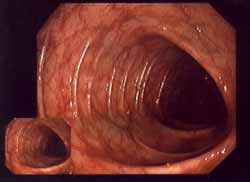

El

ácido desoxiribonucleico (ADN), esquema. El

DNS contiene grupos de nitrógeno que tienen

reacciones con el mercurio, y por eso la

substancia genética sufre un daño. La

"medicina convencional" no quiere

ver eso, y los gobiernos criminales y

calientes de la bolsa no bloquean el amalgama

hasta hoy... El ácido desoxiribonucleico (ADN), esquema. El DNS contiene grupos de nitrógeno que tienen reacciones con el mercurio, y por eso la substancia genética sufre un daño. La "medicina convencional" no quiere ver eso, y los gobiernos criminales y calientes de la bolsa no bloquean el amalgama hasta hoy...

Los elementos de la substancia genética (ADN = ácido desoxirribonucleico) contiene toda la información de la construcción del cuerpo y del metabolismo. Eso ADN contiene grupos de nitrógeno (N) que pueden reaccionar con el mercurio.

Las "letras" del ADN (incl. ADN mitocondrial) son cinco bases diversas. El mercurio se liga sobre todo al las bases timidina y uracilo, menos a adenosina, guanina o citosina. Por la formación de más radicales van ser provocados daños en la información genética, y eso puede provocar